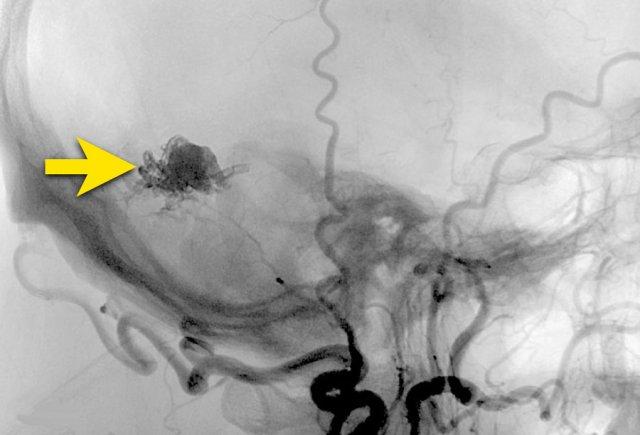

Tiếp tục với DSA…

DSA xác nhận PICA phải kèm túi phình (mũi tên) dẫn đến nidus (vòng tròn).

Nidus được dẫn lưu bởi cả tĩnh mạch nông và tĩnh mạch sâu (không hiển thị riêng biệt ở đây).

Các phát hiện phù hợp với AVM – Spetzler-Martin độ 2:

- Nidus nhỏ (<3 cm): 1 điểm

- Vị trí vùng não không chức năng quan trọng: 0 điểm

- Kiểu dẫn lưu tĩnh mạch bao gồm cả thành phần nông và sâu: 1 điểm

Túi phình hình túi xuất phát từ PICA được giải thích là túi phình liên quan đến dòng chảy.

Do sự thay đổi huyết động học gây ra bởi AVM, thành mạch có thể bị suy yếu và hình thành túi phình.

Các hình ảnh cho thấy DSA trước và sau khi đặt coil túi phình.

PICA, nidus và các tĩnh mạch dẫn lưu bất thường (cùng tạo thành AVM) vẫn còn ngấm thuốc tương phản.

Quyết định không điều trị trực tiếp AVM mà lựa chọn theo dõi và có thể can thiệp phẫu thuật trong tương lai.